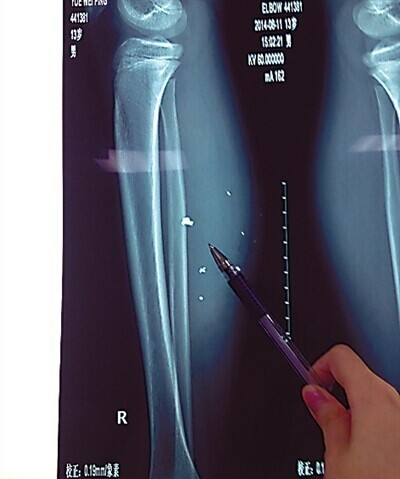

通过X光片可见,患儿右小腿皮下多处高密度影,即手机爆炸后进入小腿的异物,大约10处,需通过手术取出。